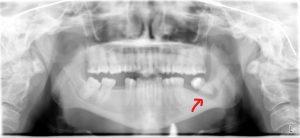

This patient had a cyst in the lower left wisdom tooth that had grown significantly. The cyst had grown to involve the nerve that runs right below it. The cyst could have progressed to injure the nerve leaving the patient with a permanent numb feeling on the cheek and teeth in that entire area of the mouth. The other wisdom teeth in the mouth had cavities and the decision was made to remove all four. The patient recovered fully from the procedure and full feeling in her mouth with no permanent damage.